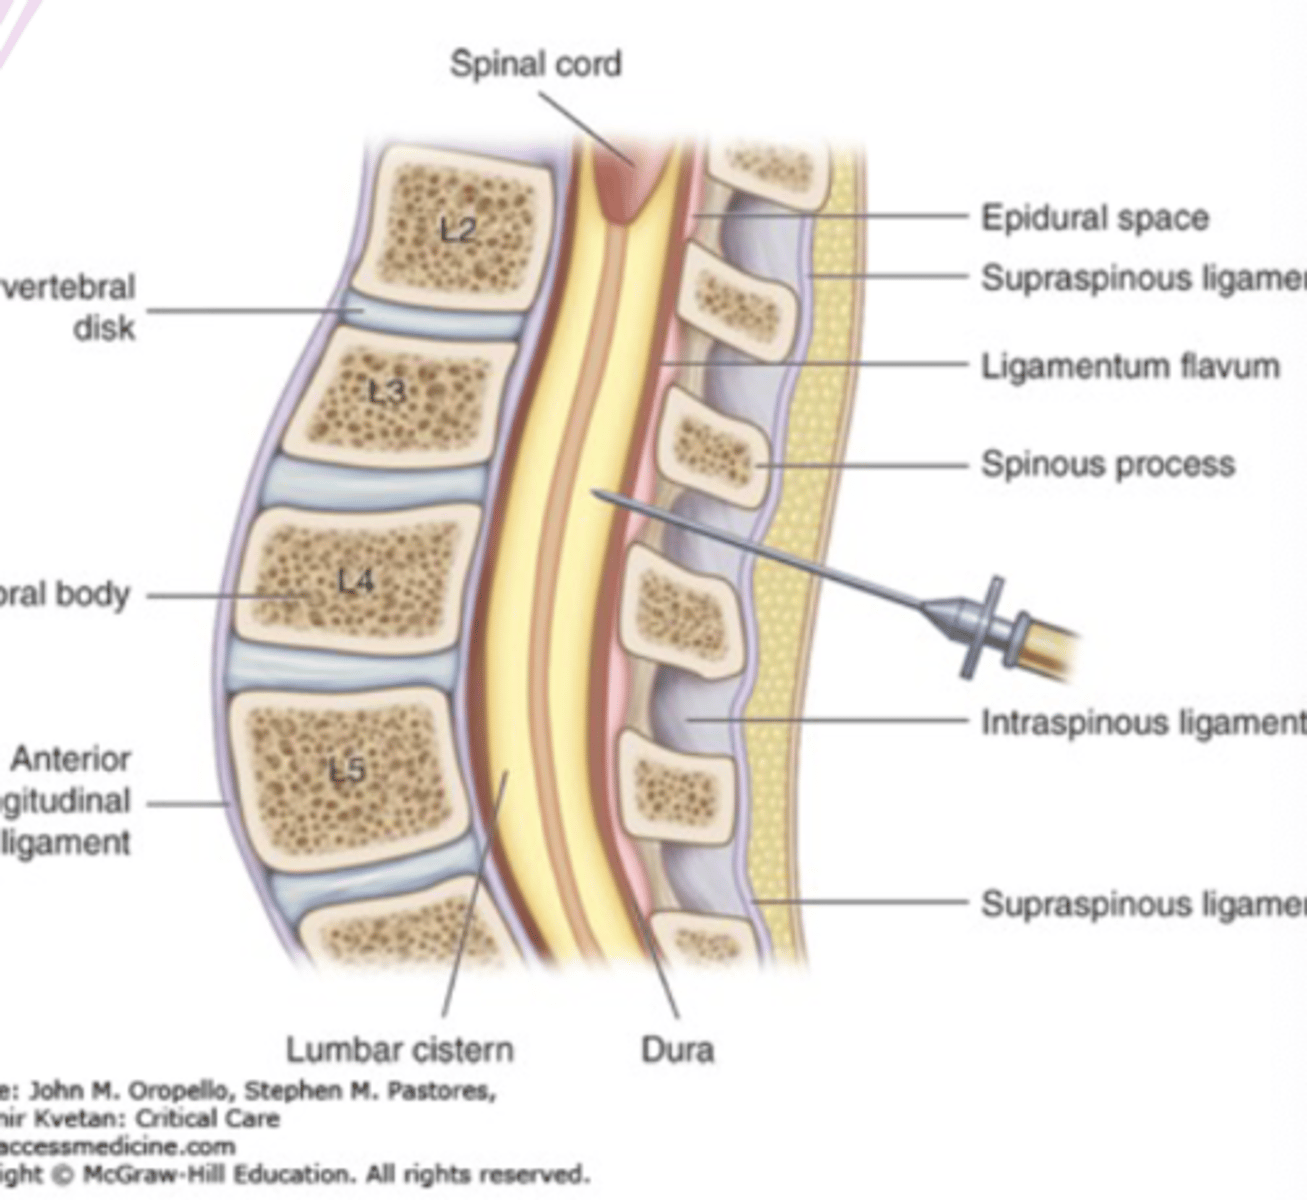

lumbar puncture

"spinal tap"

procedure of taking fluid from the spine in the lower back through a hollow needle

cerebrospinal fluid extracted

L3-L4 preferred because wider and has less soft tissue

lumbar puncture is diagnostic for

CNS infection (meningitis)

clinical concern for subarachnoid hemorrhage with a negative CT scan

lumbar puncture contraindications

infection at puncture site

acute spinal cord or head trauma

uncorrected severe coagulopathy

brain tumor

diffuse cerebral edema

lumbar puncture complication

brain herniation

headache

infection

spinal hematoma

neurologic compromise

ultrasound in lumbar puncture

reduces risk of failed or traumatic procedure, number of needle insertions